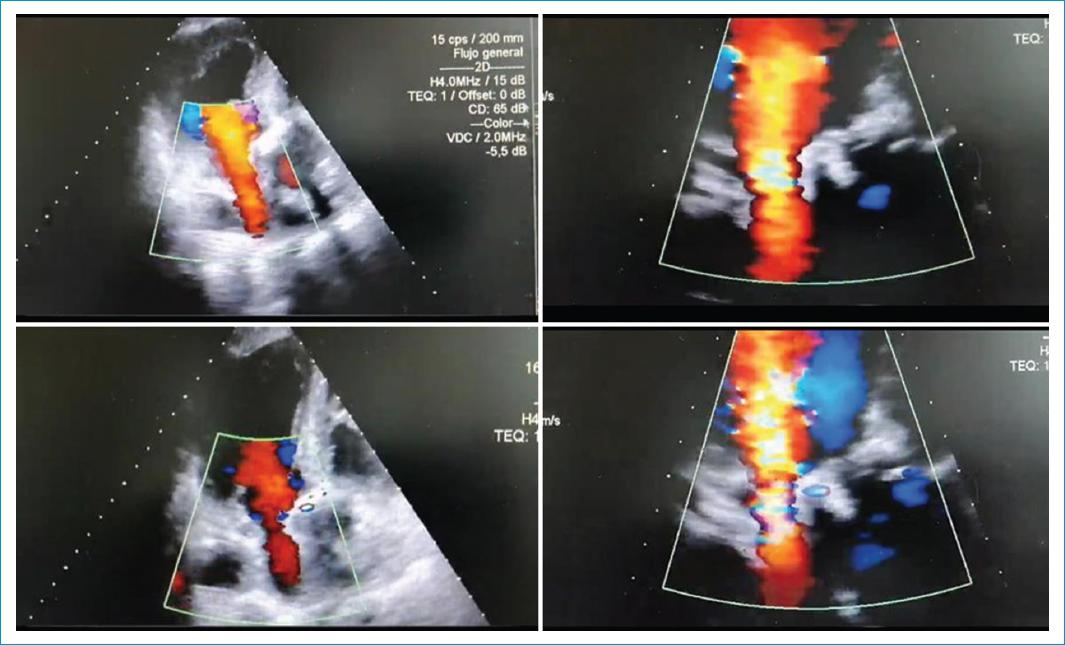

Durante la noche presentó hipotensión, disminución del gasto urinario y acidosis láctica. Se descartó trastorno de la coagulación. Se realizó ecocardiografía, la cual reportó compresión de la aurícula izquierda (Figs. 1 y 2).

Figura 1 Ecocardiografía transtorácica posquirúrgica (día 1). Ventana ecocardiográfica subcostal eje corto. A: hematoma que comprime cavidades derechas produciendo colapso sistodiastólico de éstas y aorta descendente en eje largo comprimiendo la aurícula izquierda. B: indicador blanco señalando el hematoma. C: indicador sobre la porción descendente de la aorta.

Figura 2 Ecocardiografía transtorácica posquirúrgica (día 1). Ventana ecocardiográfica subcostal, eje corto. Hematoma con taponamiento sobre las cavidades derechas y compresión de la aurícula izquierda por la aorta descendente posterior a ésta.

Durante el procedimiento, se retiró el material de sutura y los alambres esternales, y se realizó exploración, durante la cual se retiraron coágulos del pericardio, se hizo lavado de la cavidad, se revisó la hemostasia y, finalmente, se cerró por planos. No hubo pérdidas sanguíneas. Se trasladó a la UCI para continuar manejo posoperatorio (Figs. 3-5).

Figura 3 Ecocardiografía transtorácica, posquirúrgico # 2 (día 1). Ventana ecocardiográfica subcostal, eje corto. Resolución del taponamiento cardíaco derecho. Persiste la compresión sobre la aurícula izquierda.

Figura 4 Ecocardiografía transtorácica, posquirúrgico # 2 (día 1). Ventana ecocardiográfica apical 3 cámaras. A: compresión significativa de la aurícula izquierda por estructura que incluye la porción descendente de la aorta con válvula mitral abierta. B: la misma imagen anterior con la válvula mitral cerrada. Se visualiza bioprótesis normofuncionante y compresión sobre la aurícula izquierda por imagen que incluye porción descendente de la aorta. AI: aurícula izquierda; AD: aorta descendente; VI: ventrículo izquierdo.

Figura 5 Ecocardiografía transtorácica, posquirúrgico # 2 (día 1). Ventana ecocardiográfica apical 3 cámaras. Se visualiza compresión sobre la aurícula izquierda con aceleración del flujo venoso diastólico a través de ésta y bioprótesis en posición aórtica normofuncionante.